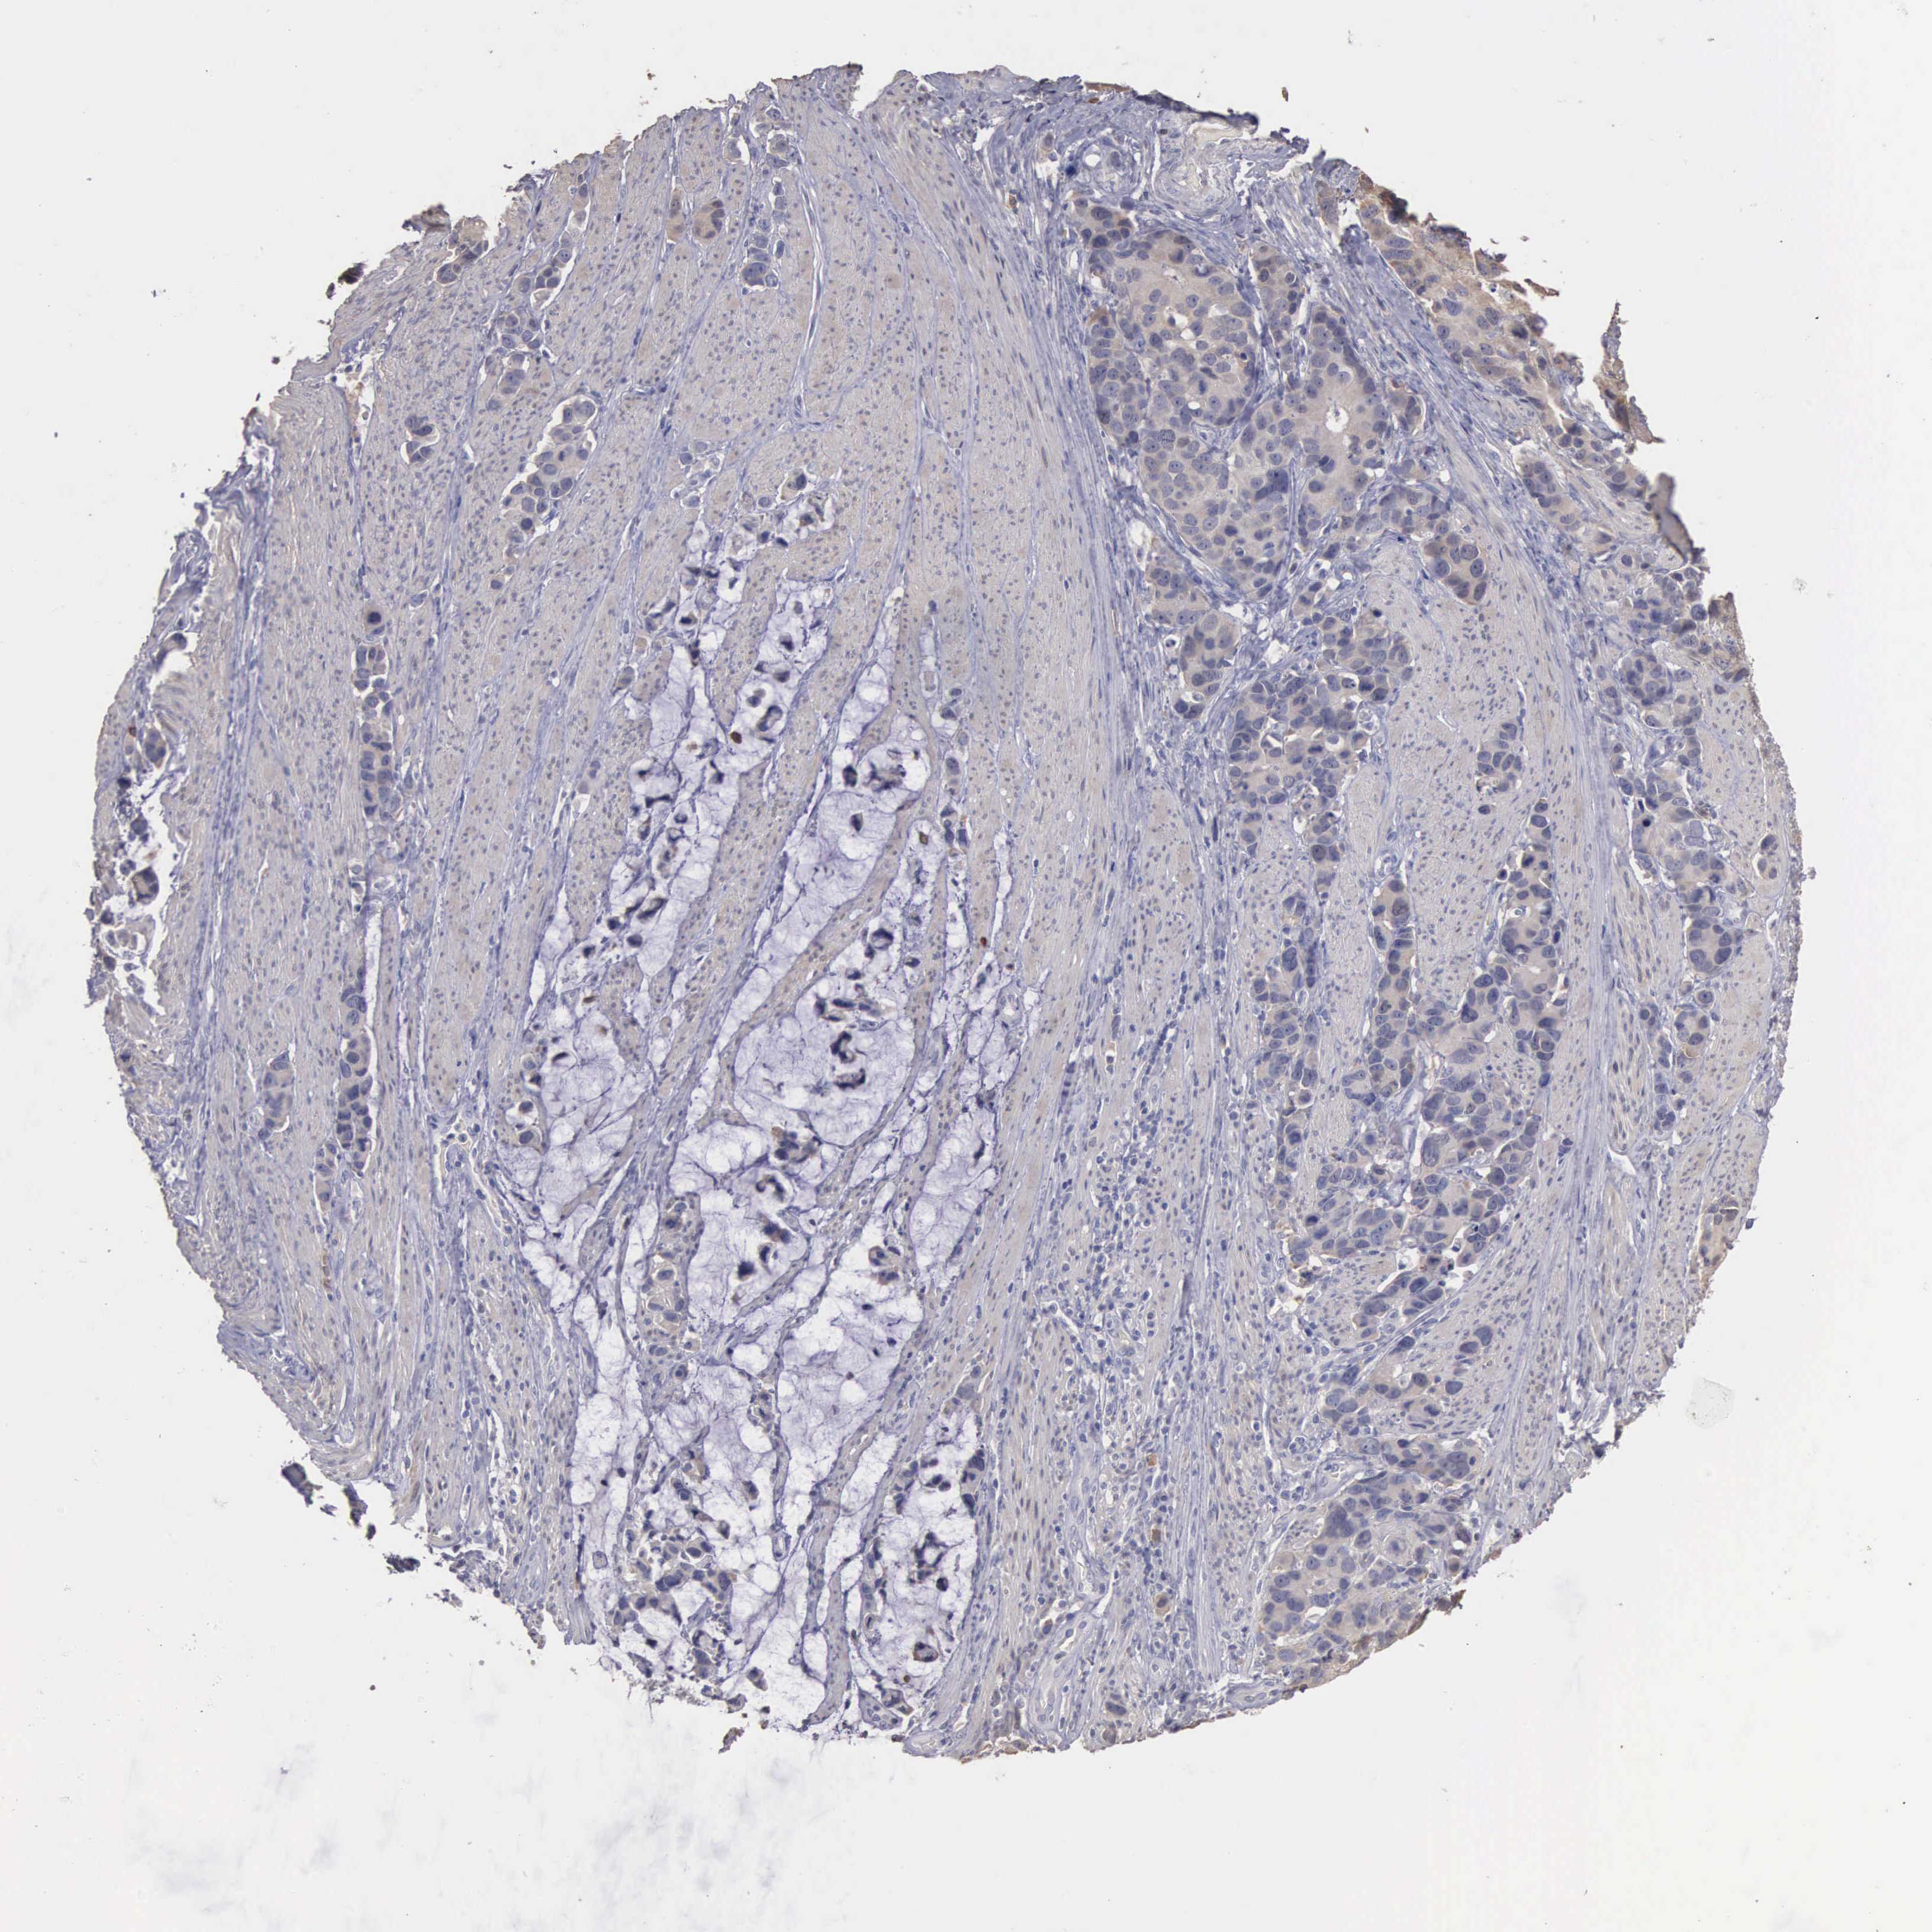

STOMACH CANCER - Protein expressioni

A mouse-over function shows sample information and annotation data. Click on an image to view it in a full screen mode. Samples can be filtered based on level of antibody staining by selecting one or several of the following categories: high, medium, low and not detected. The assay and annotation is described here.

Note that samples used for immunohistochemistry by the Human Protein Atlas do not correspond to samples in the TCGA dataset.

Antibody stainingi

Antibody staining in the annotated cell types in the current human tissue is reported as not detected, low, medium, or high, based on conventional immunohistochemistry profiling in selected tissues. This score is based on the combination of the staining intensity and fraction of stained cells.

Each image is clickable and will lead to virtual microscopy that enables deeper exploration of all samples and also displays staining intensity scores, fraction scores and subcellular localization as well as patient and tissue information for each sample.

Antibody HPA000793

Staining

High

Medium

Low

Not detected

Intensity

Strong

Moderate

Weak

Negative

Quantity

>75%

75%-25%

<25%

None

Location

Nuclear

Cytoplasmic/membranous

Cytoplasmic/membranous,nuclear

Adenocarcinoma, NOS